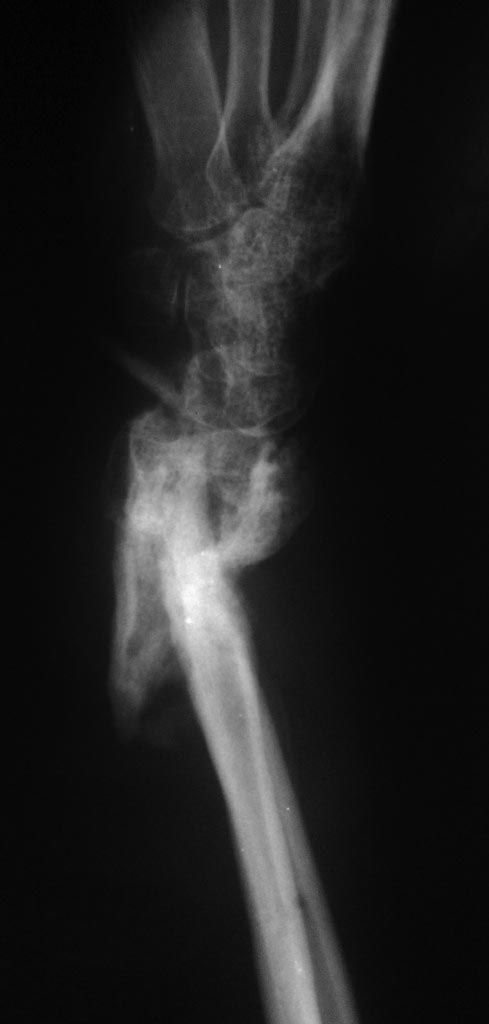

"Вышла" с 8-го этажа. Получила открытые многооскольчатые переломы обеих бедер в проксимальных отделах, открытые переломы обеих предплечий в нижней трети. Переломы бедер были фиксированы проксимальными бедренными стержнями, с предплечьями сложнее несколько: раны осложнились нагноением, были наложены аппараты внешней фиксации и на данный момент вот такая картина. Переломы бедер консолидировались. Хочется исправить деформацию. Как в таком случае лучше поступить? Выполнить адаптационную резекцию устранить деформацию лучевой кости и зафиксировать пластиной с угловой стабильностью с костной аутопластикой? Спасибо всем ответившим